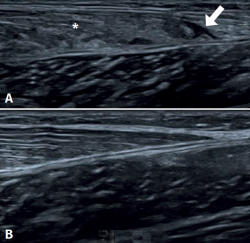

Ultrasound is the initial imaging technique of choice, due to its rapid accessibility, low cost and the absence of radiation(26,27,28), as reflected in Figure 1. Some of the features to be evaluated by ultrasound are the size of rupture, whether rupture is total or partial, and the presence of haematoma and/or fluid collections between the gastrocnemius and the soleus.

The most frequent ultrasound finding in triceps surae muscle injuries is a hypoechogenic zone at the distal myotendinous junction of the medial gastrocnemius muscle(29). The latter appears as a serohematic content between the muscle fibres and the myofascial plane, associated to an increase in echogenicity of the adjacent musculature as a manifestation of oedema and hyperaemia in the colour Doppler study(9), as can be seen in Figure 1. Delgado et al., in 141 patients clinically diagnosed with tennis leg, found that 67% of the patients presented partial rupture of the medial gastrocnemius, 1.4% presented associated plantaris tendon rupture, and 21% presented an intermuscular fluid collection between the medial gastrocnemius and the soleus muscle - thus affording an improved perspective of the possible differential diagnosis(30). On the other hand, involvement of the lateral gastrocnemius is much less common (up to 14% of the cases)(31). Ultrasound also plays a role in the lesions follow-up. In a normal evolutive scenario, we can observe gradual reduction of the oedema, resolution of the fibrillar defect and reabsorption of the fluid collections(32). It is also common to observe signs of organization of the haematoma between the gastrocnemius and the soleus, evolving as a fusiform fibrous scar without inflammatory elements, as can be seen in Figure 2.

Ultrasound allows us to distinguish between muscle injury and DVT. Up to 10% of all suspected triceps surae injuries in fact correspond to DVT, which requires specific treatment and may give rise to life-threatening complications(25). It is therefore important to maintain a high degree of suspicion of such lesions(25,30).